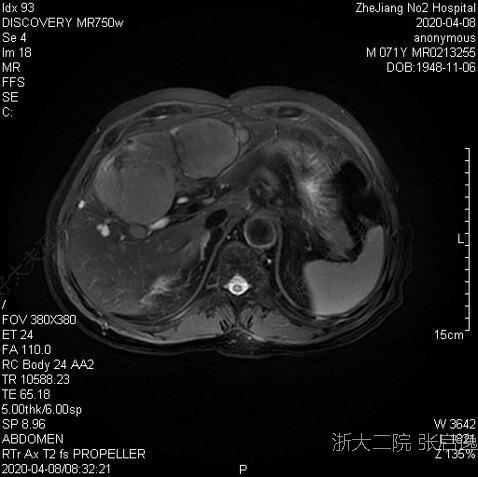

治療前65歲男性肝癌術(shù)后17年,發(fā)現(xiàn)左肝占位3個月(2020.04)乙肝:小三陽AFP:1136.3ng/ml;肝功能正常肝臟MRI(2020-04):左肝II-III及IV段肝細(xì)胞肝癌考慮,伴肝內(nèi)多發(fā)轉(zhuǎn)移灶。(IIb期)治療中2020-4侖伐替尼(8mgpoqd)+PD-13個月后復(fù)查,AFP正常,MRI顯示IV段病灶少量存活,余肝內(nèi)病灶活性消失。2021-3TACE栓塞IV段病灶治療后治療后2年現(xiàn)患者治療后2年余,MRI顯示肝內(nèi)無病灶存活,AFP持續(xù)正常。仍接受侖伐替尼+PD-1治療,不良反應(yīng)2級。